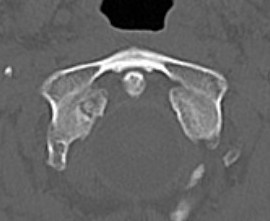

Type II: Occipital condyle fracture involving base of skull

Type III: Inferomedial alar ligament avulsion

Type II: Basal skull involvement